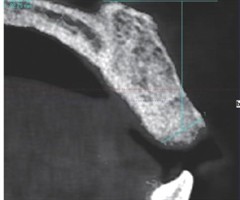

经舌腹入路取出舌根内鱼刺异物1例

[摘要]舌内异物在临床上较为罕见,其精确定位和适宜的手术路径选择对于降低手术风险和减少术后并发症至关重要。本文报道1例在影像学精确定位辅助下经舌腹入路取出舌根鱼刺异物的病例。...